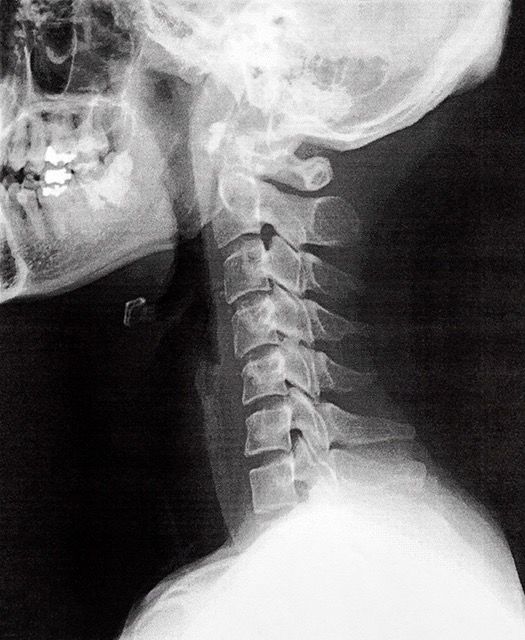

レントゲン室で撮影後、再び診察室に入ると、レントゲン写真を見ながら先生が言いました。

「まり子さん、ヘルニアや。ほら、ここの骨が。」

写真を見ると、確かに他の骨に比べ、少し元気のなさそうな(語彙力!)骨が・・・。そして先生、追い打ちをかけるように

「その下の骨、老化で少しずつ変形してきてるで」